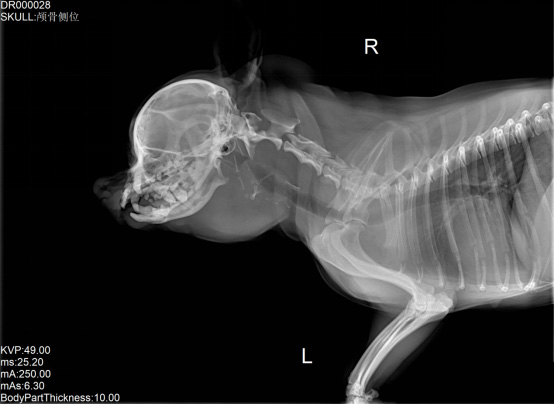

寵物DR是專業(yè)用于寵物X光拍攝的數(shù)字化X射線檢查,輔助寵物醫(yī)生進(jìn)行及時精確的診療。寵物DR主要包括五大主要部件,數(shù)字X光探測器,高壓發(fā)生器,球管,機(jī)架,寵物專用的DR工作站軟件。寵物DR由于采用數(shù)字技術(shù),自動成像處理,模擬X線圖像向數(shù)字化X線圖像的轉(zhuǎn)變。寵物DR與傳統(tǒng)模擬X光機(jī)相比有什么優(yōu)勢呢?采集時間10毫秒以下,成像時間僅為3秒,較高的空間分辨力和低噪聲率,提高了病灶的檢出率,避免漏診誤診等問題。減少X線對人體照射的不良影響寵物DR照片是您最佳的選擇。提高寵物醫(yī)生工作效率,總而言之,選擇寵物DR是寵物醫(yī)院的最佳選擇。寵物醫(yī)學(xué)影像學(xué)實現(xiàn)全數(shù)字化和無膠片化升級發(fā)展提高技術(shù)水平。